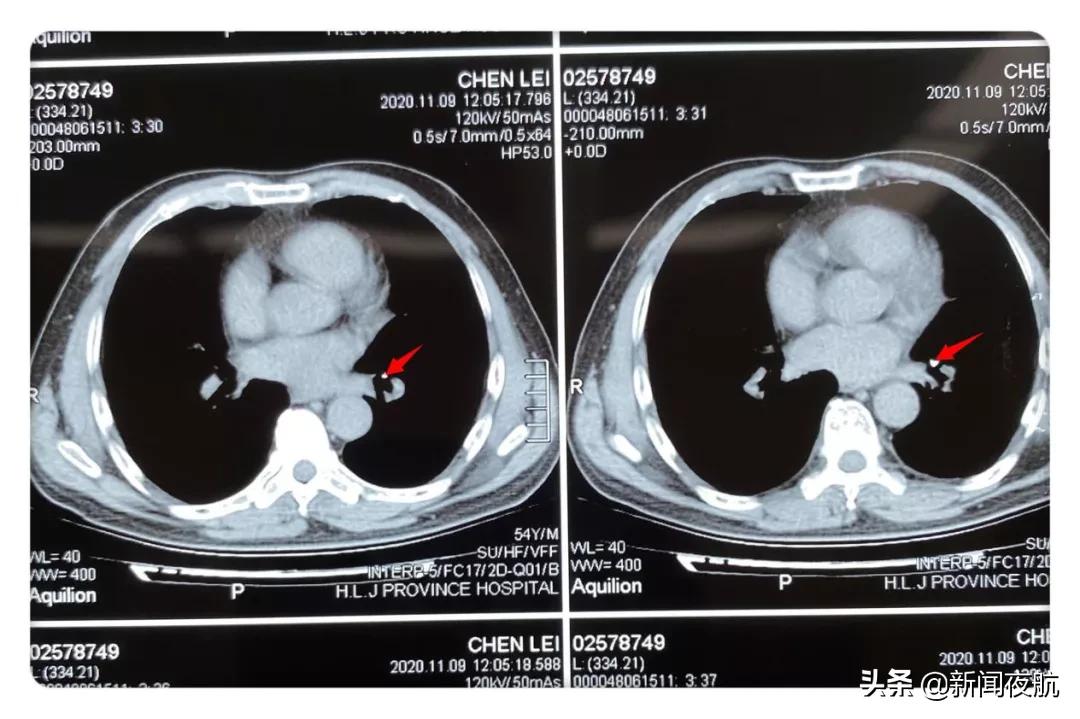

可是过了好几天,这个异物却丝毫没有动静,反而是男子觉得自己的嗓子越来越疼,于是他就来到了哈工大附属黑龙江省医院香坊院区。消化内科医生马上请呼吸内科会诊,在肺部CT中发现了异常,医生判断异物针位于左肺下叶基底段内。

箭头所指为异物